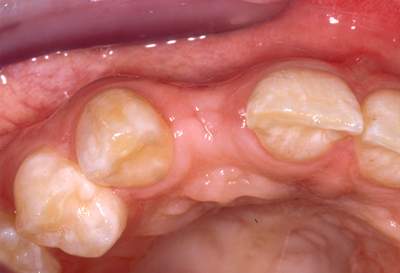

Which of the following are disadvantages of Type 1 implant placement?

There is a risk of incomplete bone fill within the peri-implant defect.

Resorption of the facial crestal bone may result in recession of the mucosa.

The defect morphology is favorable for simultaneous bone augmentation.

Flattening of the facial bone facilitates grafting of the external surface of the ridge.